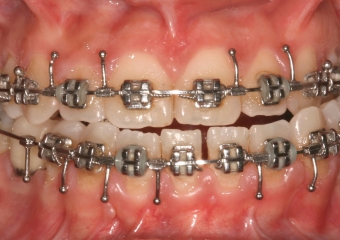

Mordida inicial

Mordida final